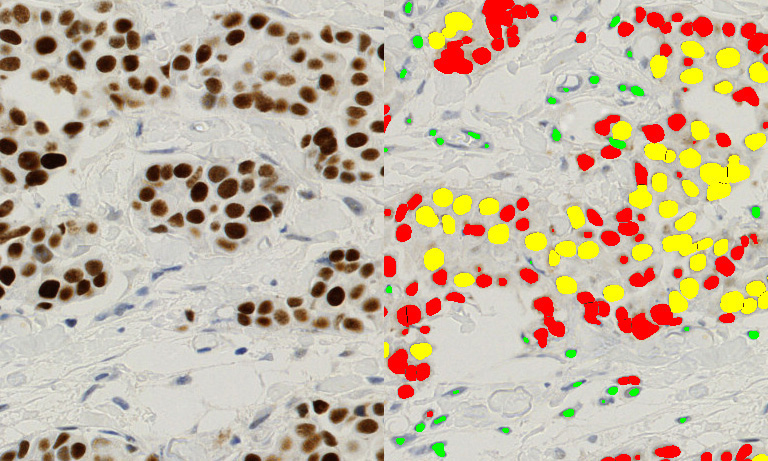

Traditional tissue research was limited to small sample areas. With whole slide imaging (WSI), you can now explore the entire specimen at multiple magnifications.

Having both brightfield and fluorescence WSI capabilities enables high-resolution digitization for spatial analysis, multiplex biomarker detection, and quantitative tissue profiling.

It delivers high-speed, high-precision scanning with exceptional image clarity and color fidelity, producing high-quality whole slide images.